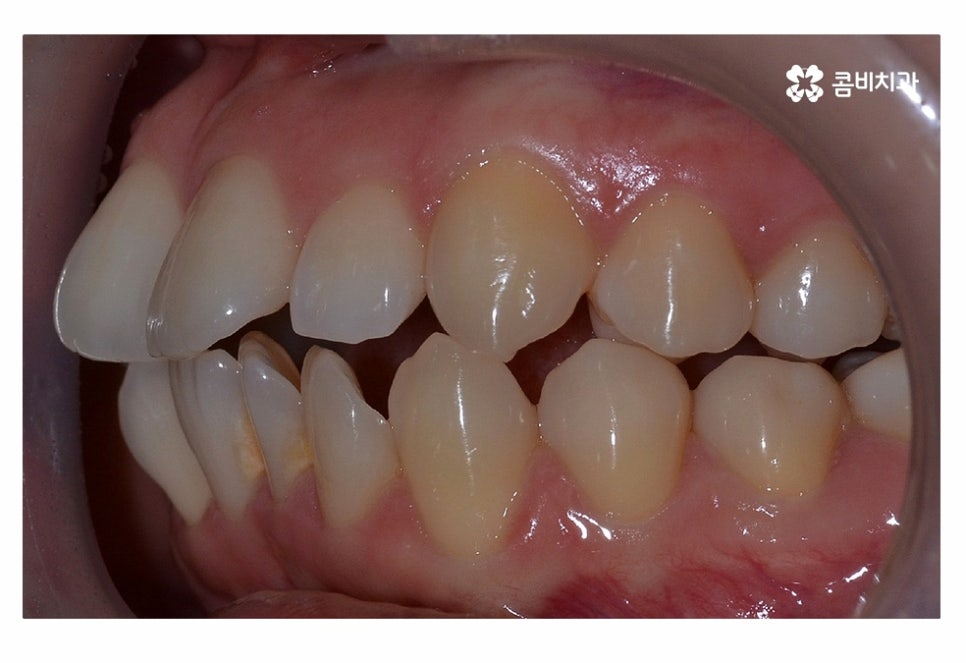

오늘은 치아부분교정 사례와 함께 부분교정에 대한 설명을

해드릴 예정이며 위 사진에서 보시는 환자분의 경우

정면에서 보는 치열과 측면의 차이가 다소 크다는 것을 알 수 있는데요.

이처럼 치열은 정면에서 보이는 것만이 아닌 얼굴형과 골격을

고려하여 치료 계획을 세워야 한다는 것을 알 수 있어요.

교합이 정상적이고 치아의 이동 공간을 고려할 때

치아부분교정이 가능했던 환자분이었기 때문에 윗니와 아랫니에

각각 부분교정이 진행된 사례라고 할 수 있는데요.